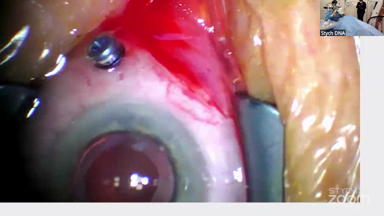

Viewer Discretion Advised: The videos may contain graphic images of surgical procedures that could be disturbing. Viewer discretion is advised. The site is intended for users who are 18 years or older, and no viewers under 18 years of age are allowed unless the use of the site is part of a class within an institution of secondary education and the viewing is supervised by an adult education professional.